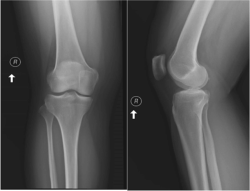

The first case was that of a 30-year-old woman who presented with 2 weeks of persistent right lateral knee pain after running. There was no specific injury. She did note that she had not run for several months preceding this and went out for about 4 miles. The knee was sore and aching at the time, but she figured it was simply related to her previous inactivity. There was mild swelling later that same evening. She treated the knee with rest, ice, and use of a nonsteroidal anti-inflammatory drug (NSAID) but noted only minimal improvement over the coming days. She presented to urgent care where radiographs were obtained and read as "normal" (see Figure 1). She was instructed on continued conservative management and to follow up with orthopaedics.

Figure 1 - Click to enlarge in new windowFigure 1. Anteroposterior and lateral views of the right knee. No evident fracture, dislocation, or other osseous abnormality to explain patient's symptoms.